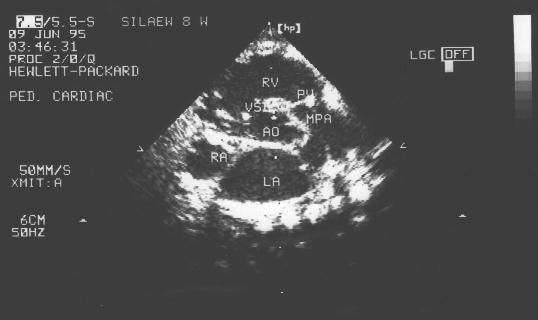

Двухмерная эхо (а,в,с): признаки незаращения межжелудочковой перегородки, смещения аорты вправо и сужения устья легочной артерии.

а)